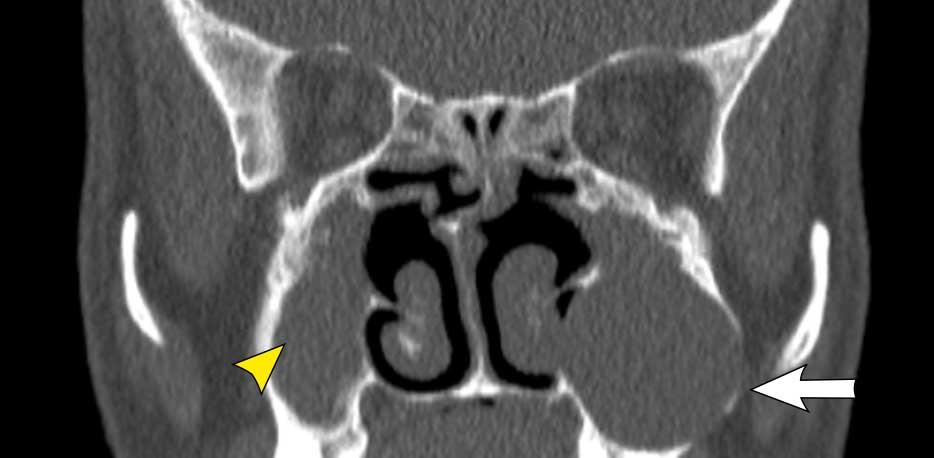

Bệnh nhân này có nang nhầy ở xoang hàm trái với giãn rộng nhẹ (mũi tên trắng).

Bên phải có một khối không có giãn rộng (đầu mũi tên vàng) và vẫn còn một ít khí trong xoang hàm.

Đây là nang ứ dịch.